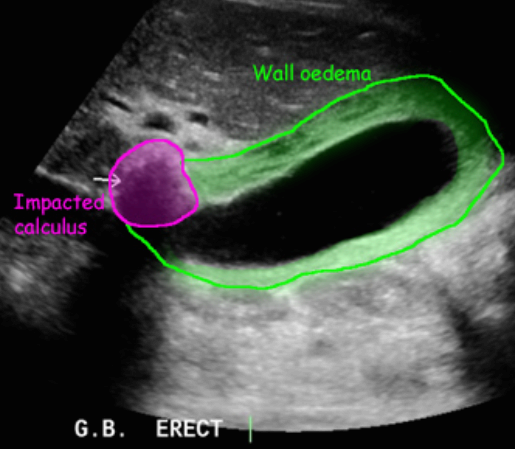

급성담낭염 US finding

- 담낭관내 결석

- 담낭벽이 두꺼워진다 ( GB wall thickness 3mm 이상)

- GB내강의 압력증가 및 확장 (width 5cm 이상)

- color doppler 시 GB wall 혈류증가 GB lumen bile sludge (내부에코증가)

- 급성담낭염은 담낭주위 액체저류 (pericholecystic fluid)

- 심한 RUQ pain (Murphy sign) : 젊은 환자에서는 대부분 Murphy sign이 있지만, 노인에서는 Murphy sign이 없더라도 급성 담낭염이 있는 경우가 많으므로 더 주의 깊게 관찰해야 한다.